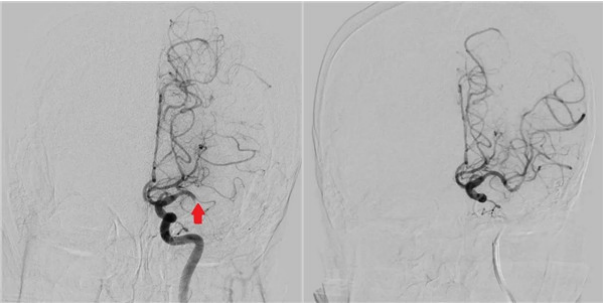

图1:左侧大脑中动脉闭塞 图2:大脑中动脉恢复通畅

面对老人的家属,医生耐心沟通手术的获益与风险,很快,家属签字同意急诊取栓手术,老人立即接受左侧大脑中动脉取栓手术。手术很顺利,用取栓支架结合抽吸,一次就取出了血栓,从开始到血管开通仅用了30分钟,即刻,老人右侧肢体的肌力就恢复了正常。

检查结果显示,老人左侧大脑中动脉主干闭塞,血管介入科医师紧急到急诊室评估病情,向家属交代急性大血管闭塞性脑梗死的危害,必须尽快开通闭塞的血管,否则老人后期会终身瘫痪,甚至面临生命危险。